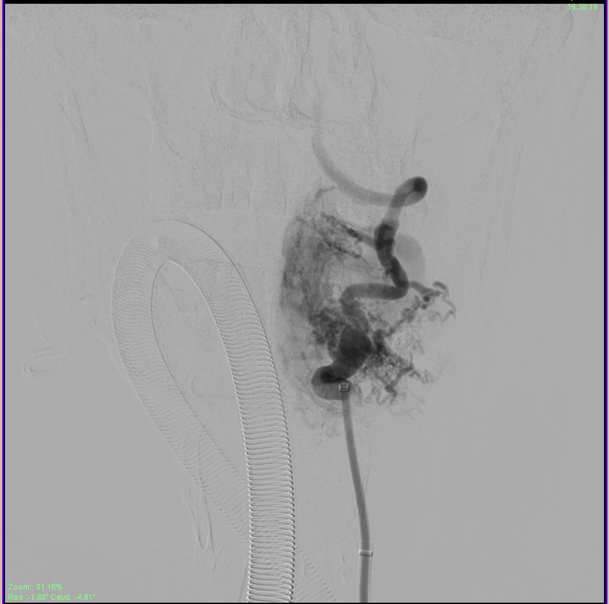

The patient was then administered general anesthetic. IV heparin of approximately 1000U was administered every hour further on and a Heparin flush was connected to the femoral sheath. The 5F short sheath was then exchanged for a Neuron Max 088 Sheath which was placed under fluoroscopic guidance into the left proximal subclavian artery. A 5F Navien catheter was then advanced into the Left Vertebral Artery railroaded on a 035 guidewire. Over this the Neuron Max catheter was moved co-axially into the proximal vertebral artery as well. An Echelon Microcatheter was then taken over the 014 Traxcess microwire and feeders from the distal V2 segment of the vertebral artery were selectively catheterized and visualized. The large lateral feeder which was significantly dilated was chosen for onyx injection (Figure 4). DMSO was injected to fill the dead space of the microcatheter and Onyx was injected under multiple blank roadmap guidance into the feeder to fill the EDAVF sac partially. Reflux into the main vertebral artery was noted, after which the injection of the onyx was stopped. Post injection films showed complete obliteration of the feeders from the vertebral artery (Figure 5).

Figure 4 Injection of the large lateral feeder showing filling of the fistula.

Figure 5 Partial obliteration of the EDAVF after onyx injection of the vertebral feeders, showing stasis in the draining veins.

The sheath was then repositioned into the left Costocervical trunk. (The Echelon microcatheter was then advanced distally into the branch over a microwire (Figure 6). Multiple vials of Onyx were injected to the fistula achieving complete obliteration of the venous sac in just over 55 minutes approximately. The Onyx was also seen filling the adjacent feeder branches as well obliterating all arterial feeders to the EDAVF. A check angiogram of bilateral subclavian arteries and the right vertebral artery showed considerable slowing of flow into the EDAVF with approximately 80-90% obliteration of the venous sac (Figure 7).